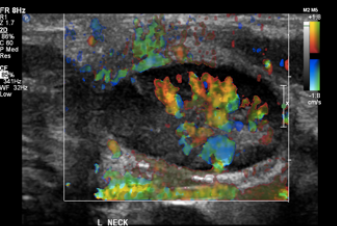

Lymphadenitis

• *Enlarged nodes**

• Normal morphology

Increased vascularity

• *Matted mass**

• Fused nodes

• *Abscess formation**

• *-** Heterogeneous mass

• Thick irregular walls

• Increased peripheral vascularity